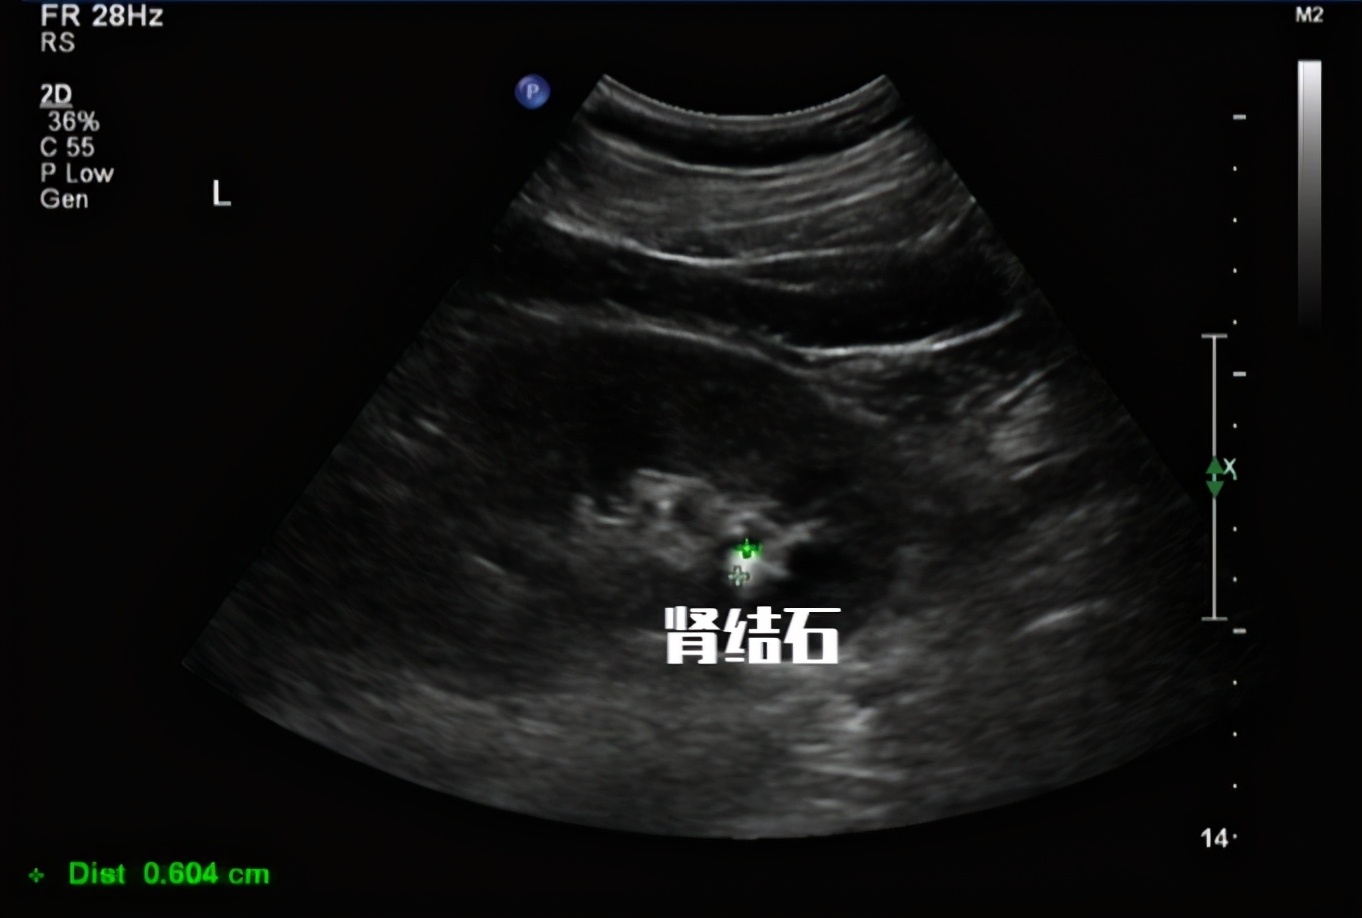

尿隐血阳性: 常见于肾脏或尿道疾病、肾性高血压、尿路结石、肾结核、恶性肿瘤、血红蛋白尿症(不同血型输血、溶血性贫血等)、肌红蛋白尿症(骨骼肌破坏)。

非肾源性血尿见于 :① 暂时性镜下血尿 ,如正常人,特别是青少年在剧烈运动、急行军、冷水浴、久站或重体力劳动后。女性患者,还应注意是否有月经血污染尿液,应通过动态观察加以区别。 ② 泌尿系统自身疾病 :如泌尿系统各部位的炎症、肿瘤、结核、结石、创伤、肾移植排异反应、先天性畸形等均可引起不同程度的血尿。 ③ 其它疾病 :见于各种原因引起的出血性疾病,如特发性血小板减少性紫癫、血友病、再生障碍性贫血和白血病合并血小板减少、DIC、高血压、动脉硬化、高热;某些免疫性疾病如系统性红斑狼疮等;泌尿系统附近器官的疾病如前列腺炎、精囊炎、盆腔炎等。